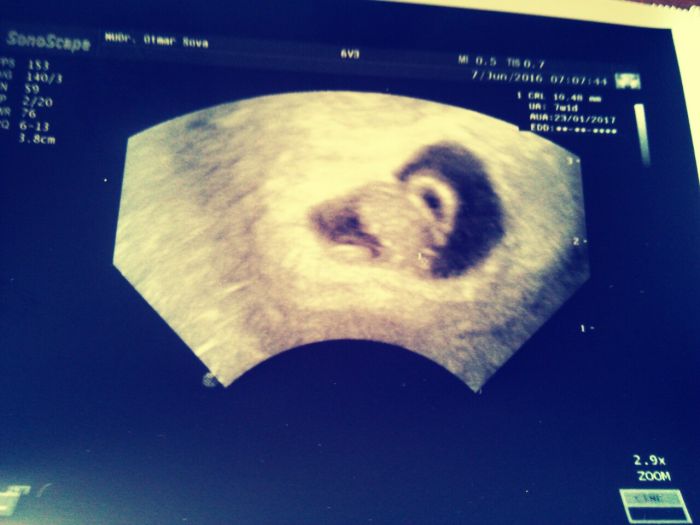

Ahojky,jsem prvorodicka... takže si dost lidi řekne že plaším :-(  snažily jsme se 4 roky.Dnes jsem 10+0.V 8tt jsem prodelala krvaceni a dostala 1-1-1 Utrogestan.Na Ult vše v pořádku,mimísek vyrostl a srdíčko bylo.Na další kontrolu jdu až 28.6 a bojim se..Nemam žádne příznaky,ze zacatku jsem mela citliva prsa a ted nic.Jen mam kovobou chut v puse a strasne slinim :-D  a obcas me je na zvraceni.Je normalni v 10 tt aby mi nebyli nic? Omlouvam se vsem,ale je to vazne vymodleme mimi.